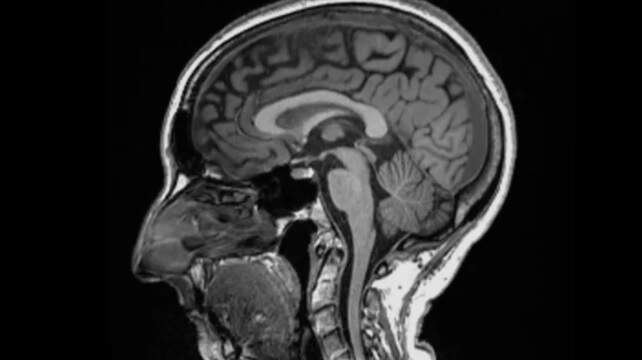

Home em foco Imagem revela como infecção por covid pode afetar o cérebro

Pegar covid pode causar alterações no cérebro, sugere um estudo publicado na revista científica Nature. Cientistas encontraram diferenças significativas em exames de ressonância magnética realizados em pacientes antes e depois da infecção.

Mesmo após uma infecção leve, o tamanho geral do cérebro havia encolhido um pouco, com menos massa cinzenta nas partes relacionadas ao olfato e à memória. Os pesquisadores não sabem ainda se as mudanças são permanentes, mas enfatizaram que o cérebro é capaz de se recuperar.

– O tamanho geral do cérebro em participantes infectados havia encolhido entre 0,2 e 2%;

– Houve perdas de massa cinzenta nas áreas olfativas e regiões ligadas à memória;